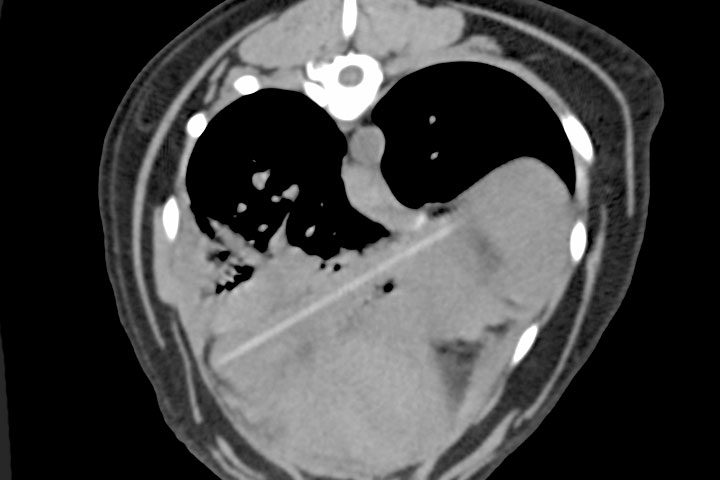

Anna Groth, RCVS and European Specialist in Diagnostic Imaging at NDSR, gives an overview of different imaging modalities used in the detection of non-GI and non-respiratory foreign bodies including how to recognise them, what they are and where they may be as well as how to manage treatment and the potential hazards.